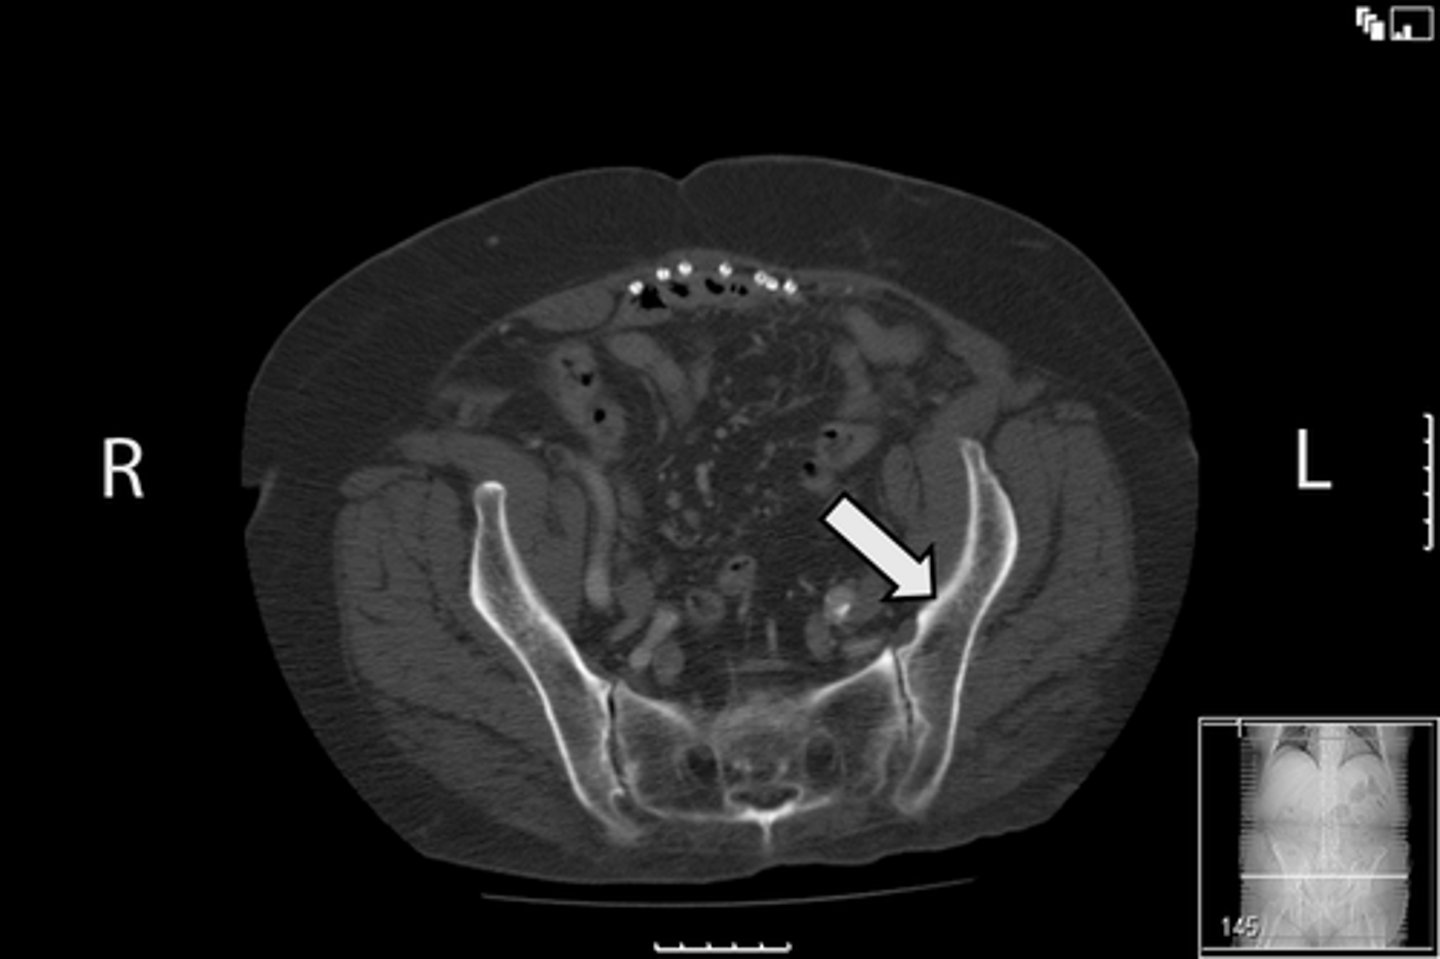

Axial bony pelvis CT

What is the image?

38

L acetabulum

<p>What is indicated in the image?</p>

New cards

What is indicated in the image?

40

L piriformis muscle

42

R piriformis muscle

44

Sacrum